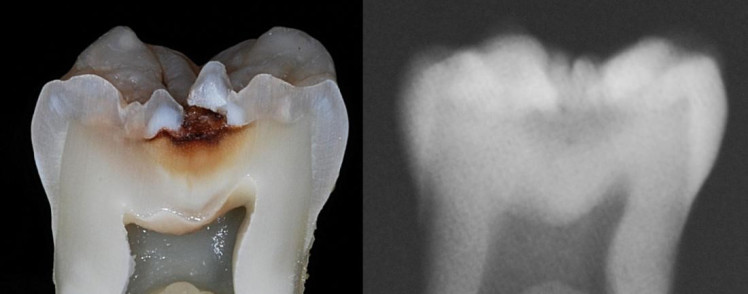

в этом случае появляется кариозный дефект в пределах эмалевого слоя. Такая форма кариеса лечится уже традиционным пломбированием. - Средняя форма кариеса (рис.2) –

в этом случае кариес распространяется за пределы эмали и поражает верхние слои дентина. В этой статье речь пойдет о лечении именно такой формы кариеса, как наиболее часто встречающейся.

- Глубокая форма кариеса (рис.3) –

в этом случае кариес распространяется на глубокие слои дентина, а пульпу зуба отделяет от кариозных тканей только узкая полоска здорового дентина. Глубокая форма кариеса лечится по особому. В этом случае применяется биологический метод